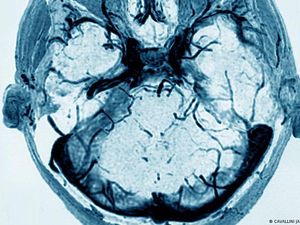

Menilik Studi soal Trombosis Pasien Covid-19 yang Picu Serangan Jantung

Viral video pengentalan darah atau trombosis yang memicu serangan jantung pada pasien Covid-19. Video tersebut merupakan hasil studi yang sudah dipublikasikan.